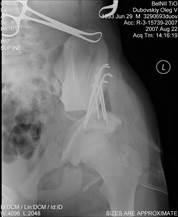

Для ранней диагностики различных проявлений дисплазии тазобедренного сустава проводится плановый осмотр грудных детей ортопедом с обязательным проведением УЗИ тазобедренных суставов, а при дисплазии — УЗИ и рентгенологические исследования тазобедренных суставов.

Все перечисленные симптомы могут наблюдаться вместе либо может иметь место только часть симптомов. При малейшем подозрении на врожденную патологию суставов ребенка направляют на рентгенографию.